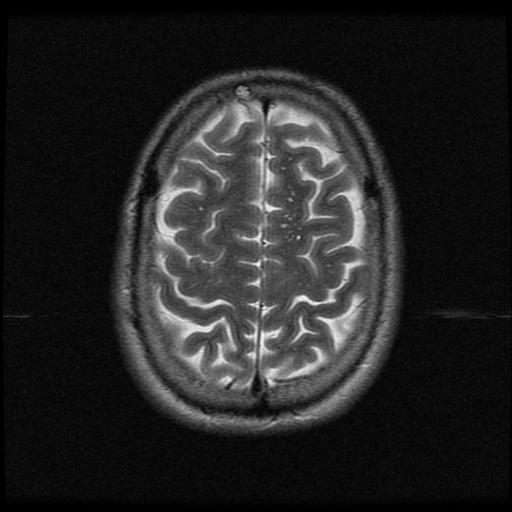

MRI Brain - Transverse

T2-Weighting

This type of MRI study looks at the brain with 20 transverse (horizontal) cuts beginning at the base and working to the top.

T2-weighting causes the nerve connections of white matter to appear gray, and the congregations of neurons of gray matter to appear white, while the CSF appears light.

These will show current disease activity if present (which there is not).